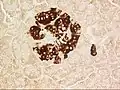

A pancreatic islet from a mouse in a typical position, close to a blood vessel; insulin in red, nuclei in blue.

The pancreatic islets or islets of Langerhans are the regions of the pancreas that contain its endocrine (hormone-producing) cells, discovered in 1869 by German pathological anatomist Paul Langerhans.[1] The pancreatic islets constitute 1–2% of the pancreas volume and receive 10–15% of its blood flow.[2][3] The pancreatic islets are arranged in density routes throughout the human pancreas, and are important in the metabolism of glucose.[4]